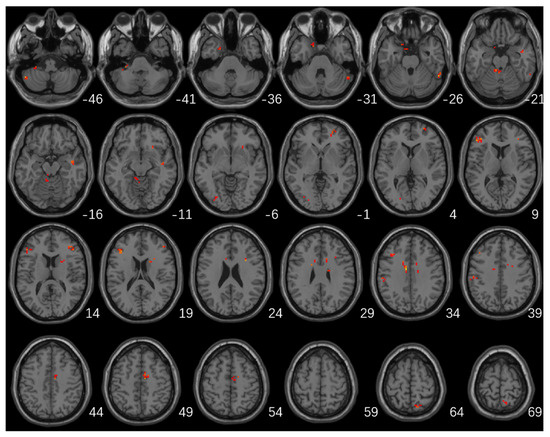

Significant differences in fALFF values among the three groups were mainly located in the left cerebellum, cerebellum posterior lobe, bilateral frontal lobes, bilateral temporal lobes, left occipital lobe, left inferior parietal lobule, right caudate, and right precuneus (Table 2; Figure 1).

Figure 1.

Brain regions with significant differences in fALFF among the three groups (GRF multiple comparison correction, p < 0.01 at the voxel level and p < 0.05 at the cluster level).

The higher fALFF values within the left cerebellum, posterior cerebellum lobe, bilateral temporal lobes, and brainstem, and the lower fALFF values within the bilateral frontal lobes, right basal ganglia areas, and left inferior parietal lobule were identified in PD-A patients compared with HCs (Table 3, Figure 2). Compared with HCs, PD-NA patients showed increased fALFF values in the left cerebellum and cerebellum posterior lobe. In contrast, decreased fALFF values were noted in the right cuneus and left superior parietal lobe (Table 3, Figure 2). When comparing the two PD groups, increased fALFF values of the right precuneus were found in PD-A patients. In contrast, decreased fALFF values were demonstrated in the bilateral frontal lobes, bilateral basal ganglia areas, left inferior parietal lobule, and left occipital lobe (Table 3, Figure 2). The fALFF values in the right precuneus (r = 0.54, p < 0.001) were positively correlated with HAMA scores of PD-A patients (Figure 3). Furthermore, the fALFF values in the left caudate were negatively correlated with HAMA scores of PD-A patients (r = −0.60, p < 0.001) according to Pearson’s correlation analysis (Figure 4).